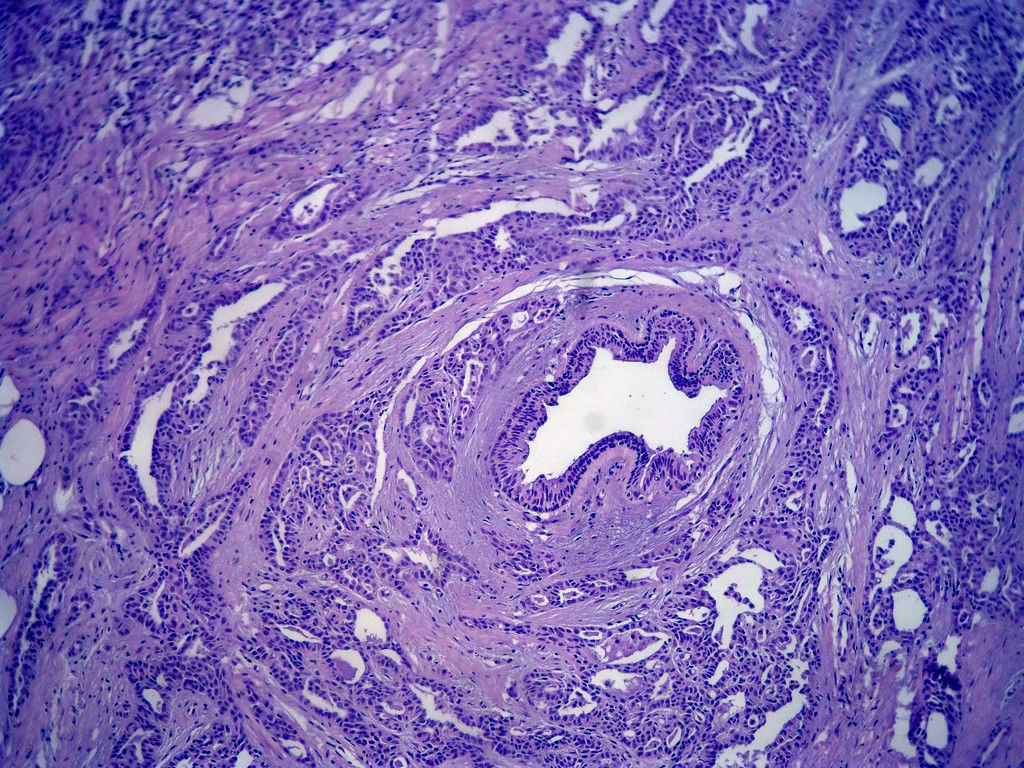

今天的一例术中冰冻。女,49岁,乳腺肿块。人气不旺,换个标题

腺病?癌?其他?(12楼常规,24楼免疫组化及会诊结果)图1

标签:浸润性导管癌 分泌癌 硬化性腺病

多谢强版主,这可是俺亲自全程操作的一张片子,俺的一点小经验是“组织要干”,“冷冻要快”,这个病例有点考验俺的神经,发上来听听高手们的意见。大体是乳腺组织一块,切面见一质硬结节,直径2cm,边界欠清,切面灰白色。强版别光夸片子漂亮啊,留下你的高见才放行

1. Most likely no invasive cancer

2 Sclerosing adenosis

3 Ductal epithelial hyperplasia

4. Bundles d Smooth muscle?

导管是乎可见双层上皮,部分上皮增生并有一定异型,考虑硬化性腺病,待石蜡。

导管可见双层上皮,部分上皮增生并有一定异型,考虑硬化性腺病

腺体与腺体之间的对比差异太大,不放心,不除外是癌,如果是我的病例,再次取材冰冻

浸润性导管癌。冰冻切片的诊断是很困难,直接诊断癌风险很大,但是在明显正常的导管间这种成片、成巢有腔的细胞团块也不是良性的表现,有的还似乎有围绕正常导管生长的倾向。诊断ADH还可以,但是不能归到任何一种DCIS的生长方式里。这例值得我好好学习。